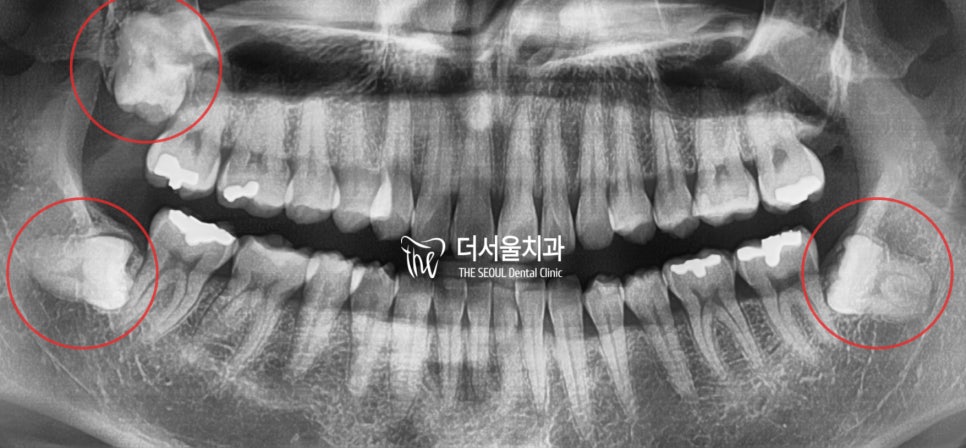

『2. 엑스레이 촬영 및 얼굴 사진』

엑스레이를 찍으면, 뼈의 모양 및 형태를

알 수 있습니다. 정면에서 찍은 것을 보니

저는 안면 비대칭이 있는 것을 볼 수 있네요.

끝으로, 파노마라 엑스레이를 찍게 되면

숨어있는 매복 사랑니 등을 확인 할 수 있습니다.